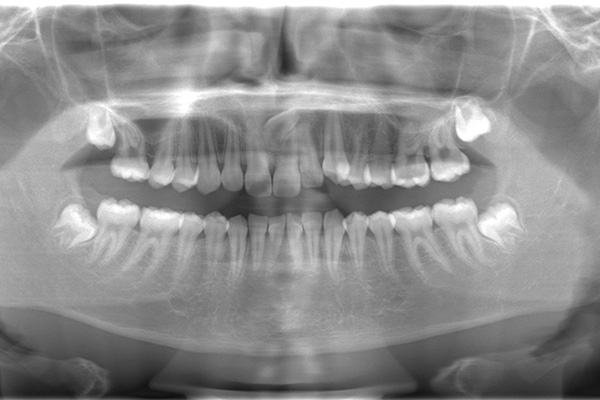

「歯に穴が空いて食事の時に痛む」という主訴でご来院されました。他院で治療を受けた箇所であり虫歯が非常に深く、通常であれば神経を全て抜く「抜髄(ばつずい)」が必要な状態でした。今回は若年者ということもあり将来的なことを鑑み神経の一部を温存する「部分的断髄法(VPT)」を提案しました。高い殺菌性と封鎖性、そして組織の再生を促す効果を持つMTAセメントを使用して神経を保護し、歯質削除量を最小限とするためコンポジットレジン修復とし、最終的には強度と審美性に優れたセラミックで再修復する計画を立案しました。

| 患者 | 10代男性 |

3年前に他院で虫歯を残した状態でドックベストセメント治療を受けられ、その後虫歯が進行してしまいました。

ラバーダム防湿を行い、無菌的な環境下で虫歯を慎重に除去。神経の露出を確認した後、炎症を起こしている一部の神経のみを除去し、残りの健全な神経を保護するためにMTAセメントを充填しました。これにより、神経の機能を維持し、歯を内部から守ることが可能となりました。